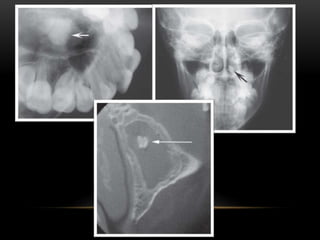

• A. Rhinolith in the maxillary sinus, seen on an OPG. The rhinolith is seen located at the posterior wall of

the right maxillary sinus (arrow), B. Rhinolith in the maxillary sinus of the same patient, seen on Waters

Projection, this projection also reveals the presence of chronic sinusitis

• Antrolith (stonein maxillary sinus) on the floor of the sinus. • It is asymptomatic.

• 70.

• A. Rhinolithin the maxillary sinus, seen on an OPG. The rhinolith is seen located at the posterior wall of the right maxillary sinus (arrow), B. Rhinolith in the maxillary sinus of the same patient, seen on Waters Projection, this projection also reveals the presence of chronic sinusitis